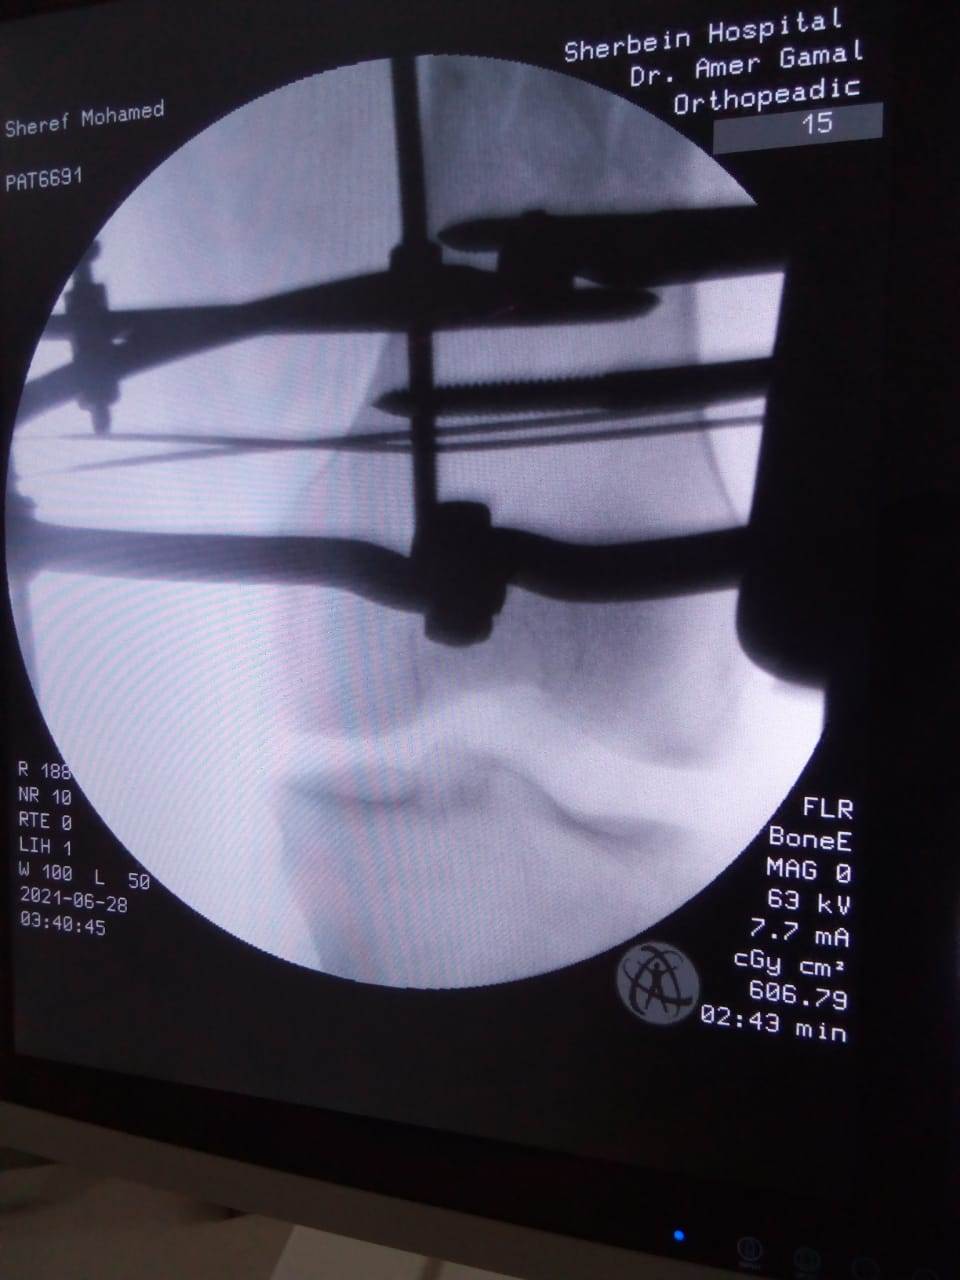

حيث تم إجراء تدخل جراحي دقيق لشاب يعاني من كسر مضاعف من الدرجة الثالثة، إثر طلق ناري، أدى إلى تهتك بالأنسجة، وكسور متفتتة بالفخذ، وذلك عن طريق جهاز "الليزاروف"، وتعد واحدة من عمليات العظام الكبرى والمتقدمة ذات المهارة الخاصة.